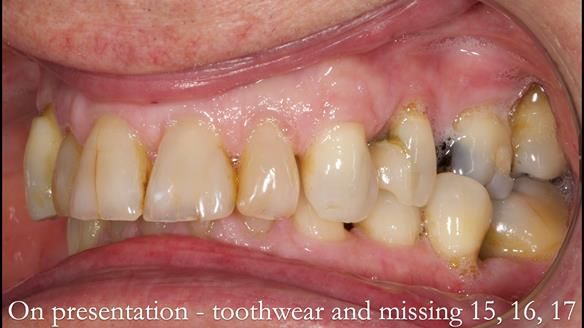

Welcome to Newsletter 64. I'll walk you through the process of providing a Mk 2 metal-based partial denture (RPD), for Ian a retired Veterinary Surgeon aged 78. The RPD was made at an increased vertical dimension and acted as an occlusal stabilisation splint - reducing the wear and bite force on the remaining natural teeth.

Ian was referred to me by his general dentist.